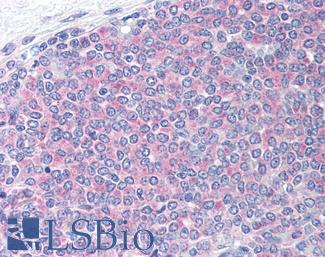

PD1 (PDCD1 / CD279)

Anti-CD279 / PD-1 antibody IHC of human tonsil. Immunohistochemistry of formalin-fixed, paraffin-embedded tissue after heat-induced antigen retrieval. Antibody LS-B7883 dilution 20 ug/ml.